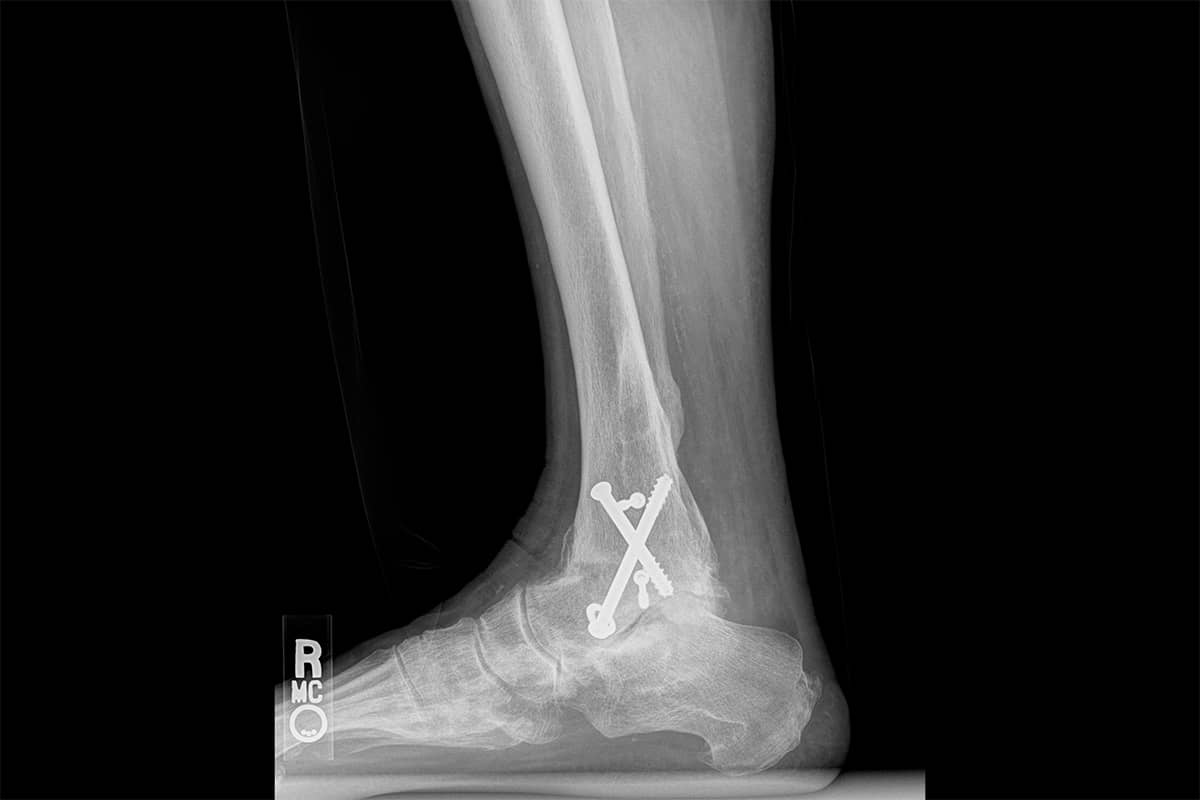

When bones in joints are broken, they sometimes heal poorly. The joint may be misaligned. The cartilage surfaces wear off, and bone-on-bone grinding occurs. Pain at these destroyed joints, especially in the ankle or foot, becomes disabling. The solution offered is often a fusion of the bones to stop the motion: the grinding cycle of pain and inflammation.

Fusion is a failure of our knowledge and skills to find a way to restore motion. When an ankle is fused, the joints below the fusion are subjected to increased loads and abnormal motion. The cartilage wears off, and the joint eventually develops arthritis. The gait of the patient after an ankle fusion is often much better than when the joint was painful, yet it is never normal. The abnormal wear patterns cause problems at the knees, hips, and back as a result of the altered gait mechanics. Artificial joint replacements for the ankle and joints of the foot are uncommon and less successful than replacements at the knee or hip due to the very small bony surfaces that must absorb the entire body’s weight with walking, running, or jumping.

We take a dramatically different approach. When presented with these often collapsed and completely worn-out ankle joints, we recreate the joint space, then add a cartilage paste to the exposed bone. This approach works well enough to preserve motion and return many people to varying levels of sports, but it by no means creates a normal joint. Given that the alternative is living with pain or having a fusion, the downside risk seems small.